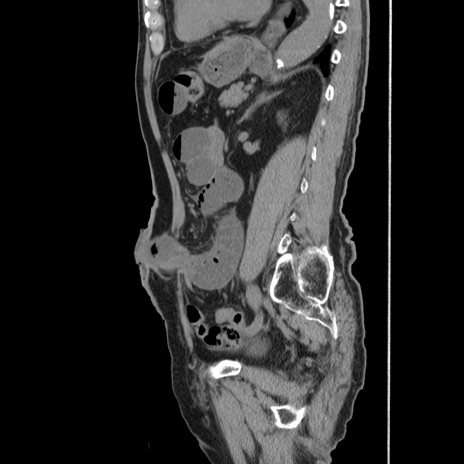

横断像

【症例】80歳代男性

【主訴】左側腹部痛、嘔吐

【現病歴】本日早朝より左腹部に痛みあり。昼頃嘔吐認めたため、救急要請。

【既往歴】直腸癌(Mile手術)、胆摘

【身体所見】意識清明、BT 35.9℃、BP 221/93mmHg、SpO2 97%(RA) 、腹部:左ストーマ周囲に限局性の腹部膨隆あり。 膨隆部自発痛・圧痛あり・軟。

【データ】WBC 7700、CRP 0.09